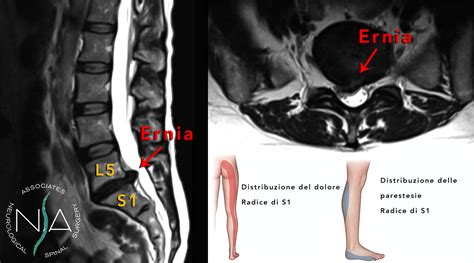

Le ernie discali lombari, che colpiscono le vertebre L4-L5 o L5-S1, sono le più comuni. I sintomi possono includere:

- Sciatalgia o Cruralgia: Dolore che si irradia lungo la parte posteriore della gamba (sciatalgia) o lungo la parte anteriore della coscia e della gamba (cruralgia). Questo sintomo indica l'irritazione o la compressione del nervo sciatico o crurale.

- Formicolii e Intorpidimento: Sensazioni di formicolio, puntura di spillo o intorpidimento lungo la gamba, il piede o le dita.

- Debolezza Muscolare (Ipostenia o Parestesia): Riduzione della forza muscolare in specifiche aree della gamba o del piede, che può portare a difficoltà nel camminare o nel sollevare il piede. Nei casi più gravi, si può manifestare una vera e propria paresi (parziale perdita di movimento).

- Risonanza Magnetica Nucleare (RMN): Attualmente è il gold standard per la diagnosi delle ernie discali. La RMN fornisce immagini dettagliate dei tessuti molli, permettendo di visualizzare con precisione l'ernia, la sua estensione e il suo impatto sulle strutture nervose. Tuttavia, è importante notare che la RMN può mostrare alterazioni discale anche in assenza di sintomi, e la sua interpretazione deve essere sempre correlata al quadro clinico del paziente.